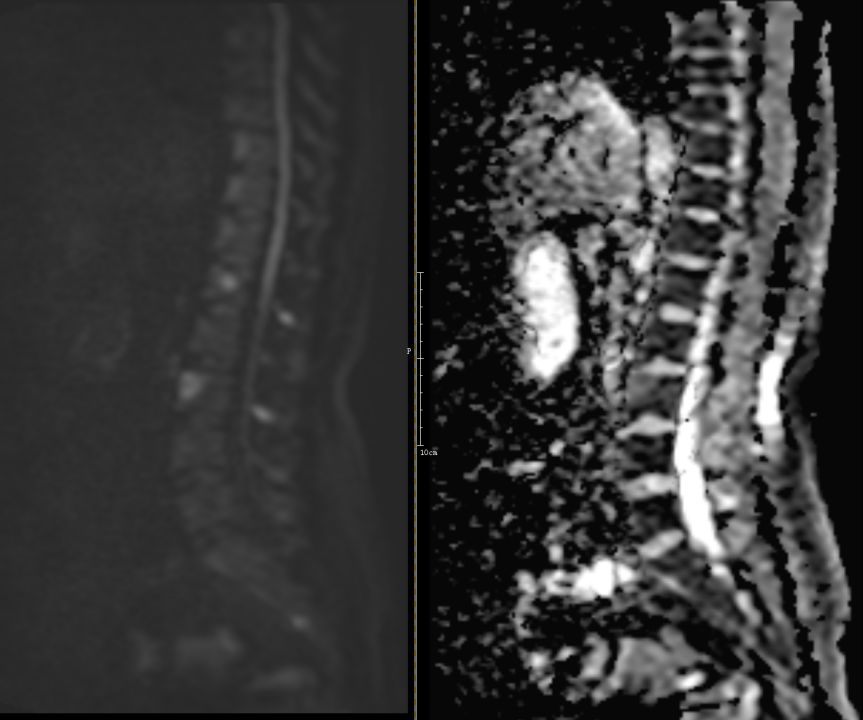

转移瘤:有肿瘤病史,病变很少累及椎间盘,多个椎体溶骨性或膨胀性破坏,肿瘤易侵犯附件、椎管或椎旁。

MRI示 部分椎体及附件信号异常,T1WI及T2WI呈低信号,STIR序列呈明显高信号,DWI序列呈高信号。考虑为转移瘤。